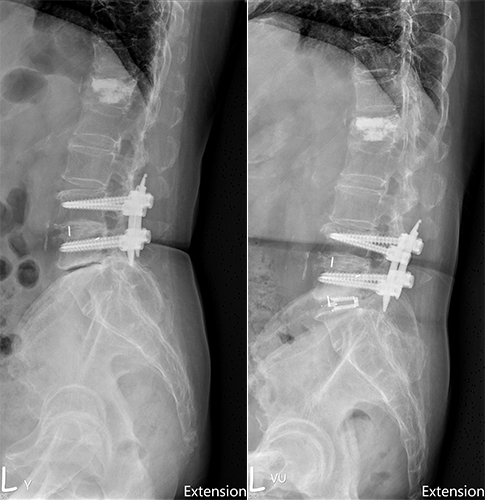

手術前及手術後。(圖片來源:陳晉瑋醫師提供)

79歲的陳女士,因左下肢麻木且行走困難已數月至門診求診,過去腰椎曾經手術過,影像檢查發現腰椎第四五節椎間融合術後的鄰近節,第五腰椎第一薦椎椎間盤因應力轉移,出現椎間盤空洞化、椎管狹窄及黃韌帶增厚等問題,有鑑於病人主要問題是單節段鄰近節狹窄及椎間高度喪失,且原先植入螺釘並沒有鬆動或失穩需延長固定,因此,陳女士接受微創可撐開式椎間融合術,改善神經痛及跛行的困擾,並縮短了復原時間。

治療選擇方面,傳統翻修(移除舊螺釘並延長內固定或重新固定)通常提供較確實的即時穩定與重建脊椎矢狀面,但伴隨較長手術時間、更多出血、軟組織剝離、感染與新螺釘固定相關併發症。若主要症狀為椎管狹窄及局部椎間高度喪失,後路單獨式可撐開椎間融合器是一個可考慮選項,更適合高齡或不宜大範圍手術的病人群。

陳晉瑋說,可撐開設計的椎間融合器在術中可恢復較大椎間高度與椎間角度(lordosis),有利於解除神經壓迫,但在骨質差或脊椎動態不穩定病人,臨床系列報告顯示單獨式椎間融合器仍有下陷及後移的事件發生,應謹慎評估個案是否符合適應症。